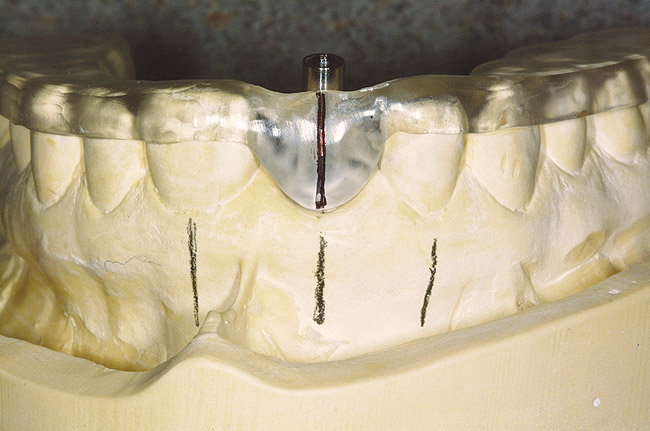

Another concern for loading of dental implants is implant alignment. When placing implants for the edentulous patient and an overlay or hybrid restoration is planned, the implants should then be placed as parallel as possible and slightly lingual to the actual tooth position. This allows establishment of normal contours of the prostheses and space for placement of the prosthetic teeth. Implants should not be placed in the central incisor region for a maxillary overlay prosthesis because this will compromise palatal contours, thereby affecting speech and tongue function. If, however, implants are planned for the partially edentulous patient and the replacement is for a natural tooth or teeth, then implants should be placed more in line with the long axis of the natural root. Teeth are designed to better handle the multitude of directional loads encountered during mastication when properly aligned on their bony base. Implants placed more in line with natural tooth roots that are properly positioned on their bony base may allow implants to better endure the various functional loads while promoting the continual physiologic bone remodeling necessary for long-term implant survival (Figure 6 and Figure 7). Depending on the type of anticipated function and the presence or signs of parafunctional habits, use of a maxillary biteplane/nightguard may be indicated (Figure 8). This can reduce the possibility of lateral loads, which have a detrimental effect on the dental implant(s). The biteplane is adjusted in centric relation with simultaneous occlusal contacts and shallow anterior guidance.

Figure 8  A maxillary biteplane/nightguard adjusted to centric relation.

Figure 8